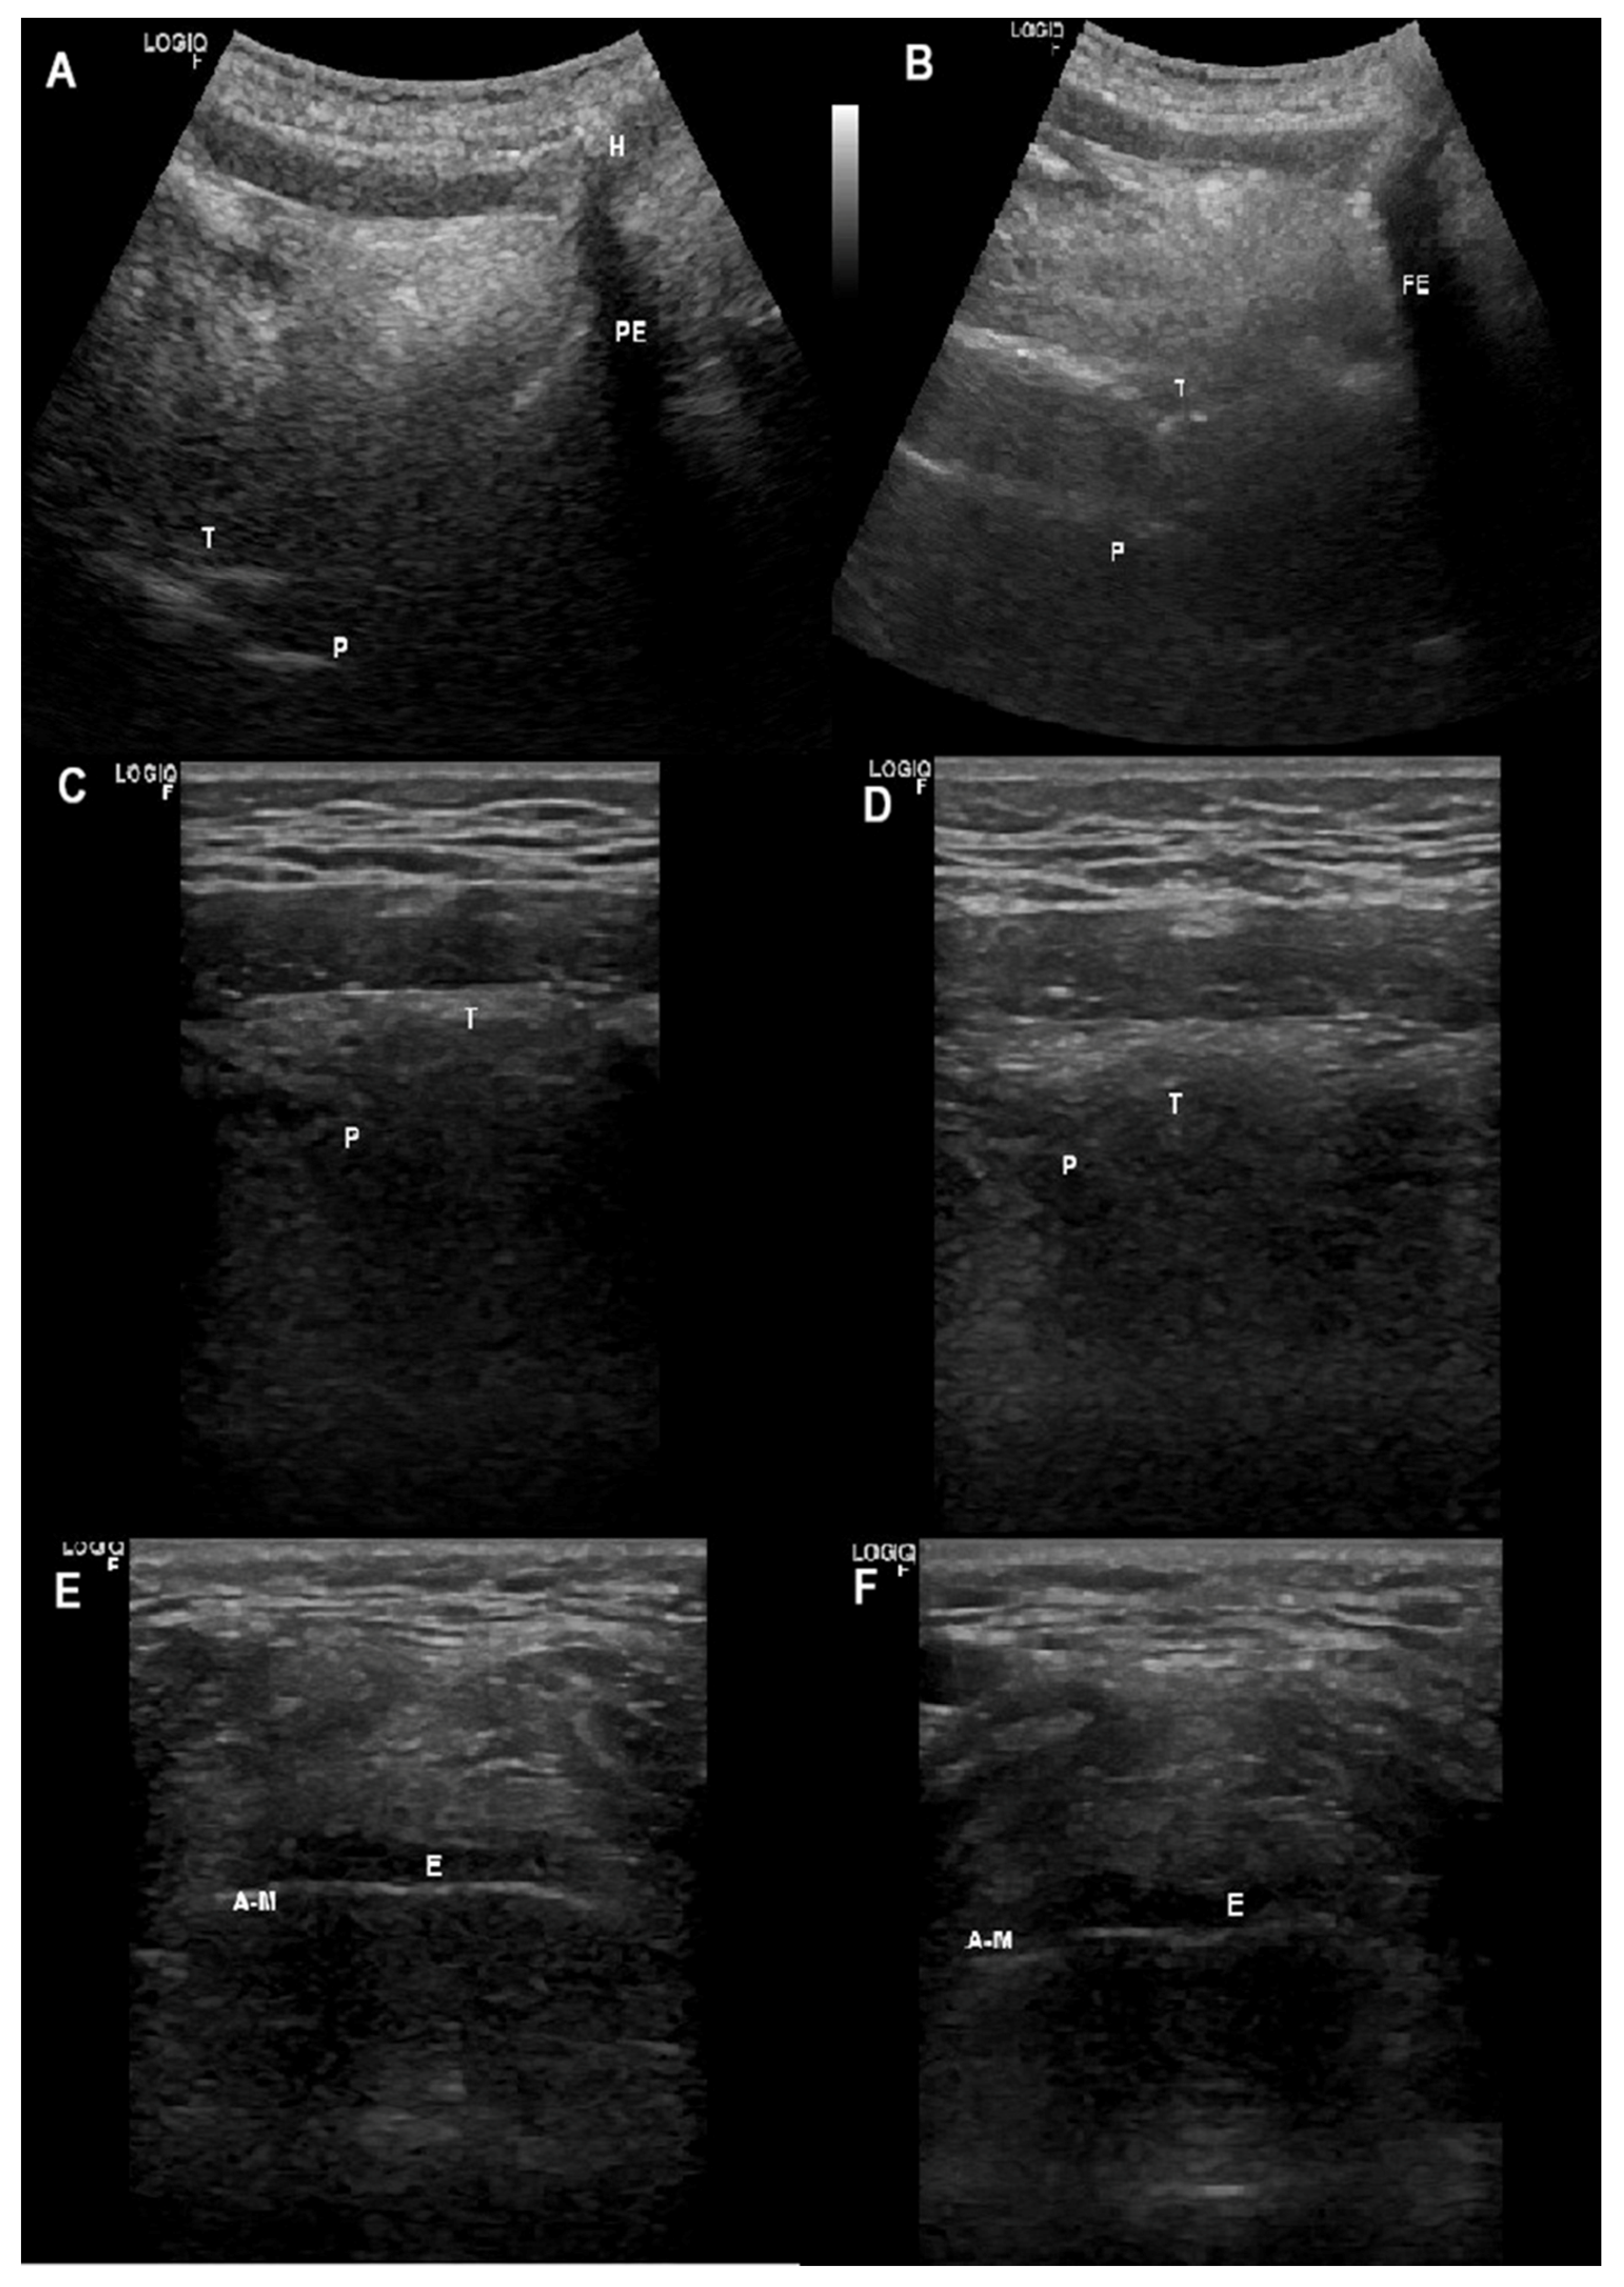

2.7.1. Ultrasonographic Upper Airway Structures

Supra-Glottis

Oropharynx

- Brekka, A.K.; Vollsaeter, M.; Ntoumenopoulos, G.; Clemm, H.H.; Halvorsen, T.; Roksund, O.D.; Andersen, T.M. Adjustments of non-invasive ventilation and mechanically assisted cough by combining ultrasound imaging of the larynx with transnasal fibre-optic laryngoscopy: A protocol for an experimental study. BMJ Open 2022, 12, e059234. [Google Scholar] [CrossRef]